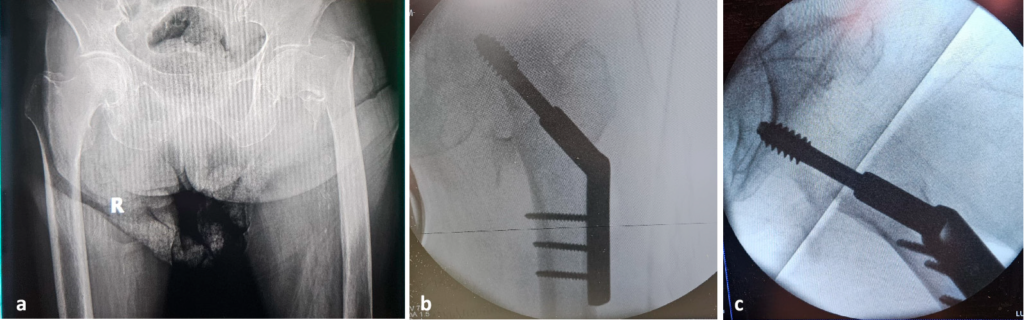

lateral view. Copyright Simona Cavalu et al.

The radiological examination reveals a per-trochanteric comminuted fracture with medial displacement of the lesser trochanter and atherosclerosis of the deep femoral artery.

Angio-CT investigation was performed, identifying a lesion in the deep femoral artery, within the area of the most distal screw.